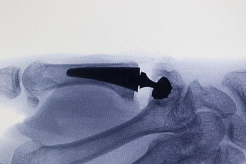

X-Ray’ler genellikle OA’yı doğrulayacaktır (Şekil A).

1. CMCJ ARTRİTİNDE DOKUNMATİK PROTEZ